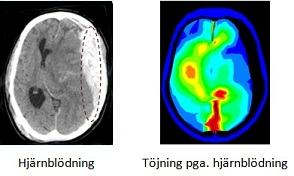

Figurerna nedan visar ett preliminärt resultat av metoden. Den vänstra figuren visar ett tvärsnitt av patienten hjärnan med blödning från CT-data. Den högra figuren visar den simulerade deformationen i färgskala. Skalan går från blå (låg deformation) till röd (hög deformation).